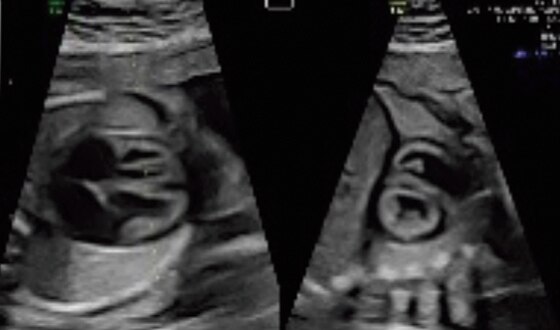

3VV and LVOT with Radiantflow™ in Dual Display